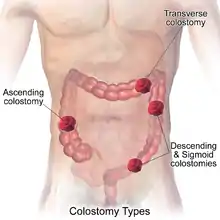

Types of colostomy include:[1][2]

- Loop colostomy: This type of colostomy is usually used in emergencies and is a temporary and large stoma. A loop of the bowel is pulled out onto the abdomen and held in place with an external device. The bowel is then sutured to the abdomen and two openings are created in the one stoma: one for stool and the other for mucus.

- End colostomy: A stoma is created from one end of the bowel. The other portion of the bowel is either removed or sewn shut (Hartmann's procedure).

- Double barrel colostomy: The bowel is severed and both ends are brought out onto the abdomen. Only the proximal stoma is functioning. Most often, double-barrel colostomy is a temporary colostomy with two openings into the colon (distal and proximal). The elimination occurs through the proximal stoma.

Placement of the stoma on the abdomen can occur at any location along the colon, but the most common placement is on the lower left side near the sigmoid where a majority of colon cancers occur. Other locations include the ascending, transverse, and descending sections of the colon.[4]